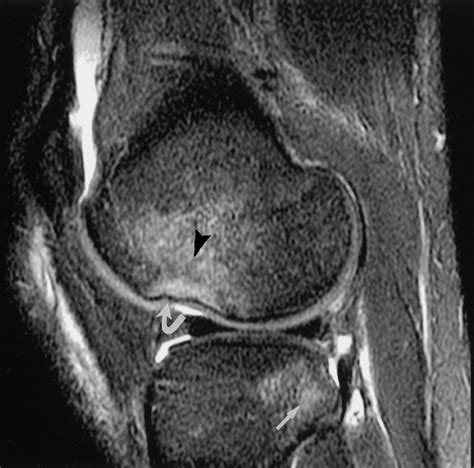

• Imaging Tests: X-rays, MRI, or CT scans may be used to visualize the bone and surrounding tissues. MRI is particularly useful for detecting bone contusions.